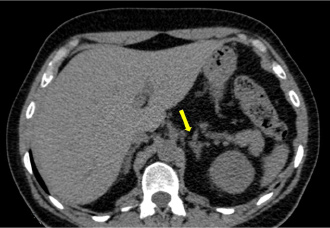

The abdominal CT scan report did not mention adrenal anomalies but on review the left adrenal image suggested nodular hyperplasia (Figure 2), while the right adrenal appeared normal.

Figure 2: Pre-surgical abdominal CT scan of the patient, showing an enlarged and irregular left adrenal not suggestive of adenoma